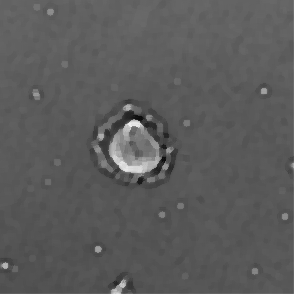

Figure 3: Original images of sequence is example of high dynamics of cell behavior affecting on contrast properties

The Fig.3 is representing couple of frames of sample image sequence with relatively high contrast between foreground and can be segmented with almost 95% accuracy with any method we used. Frame 1 of sample sequence presented at Fig.3(a) contain regions of hyper contrast pixels. In this case such condition does not affect on valid recognition since they are belong to object and present on margins of it and differs well from background. For Frame 2 there is absence of such pixels (Fig.3(b)) and this conditions also makes segmentation possible in relatively inflexible filtering conditions. The Frame 2 has relatively low contrast however it is seen that after filtration applied on image we achieve good difference of core and cell body compared to background as it presented at Fig.4 .